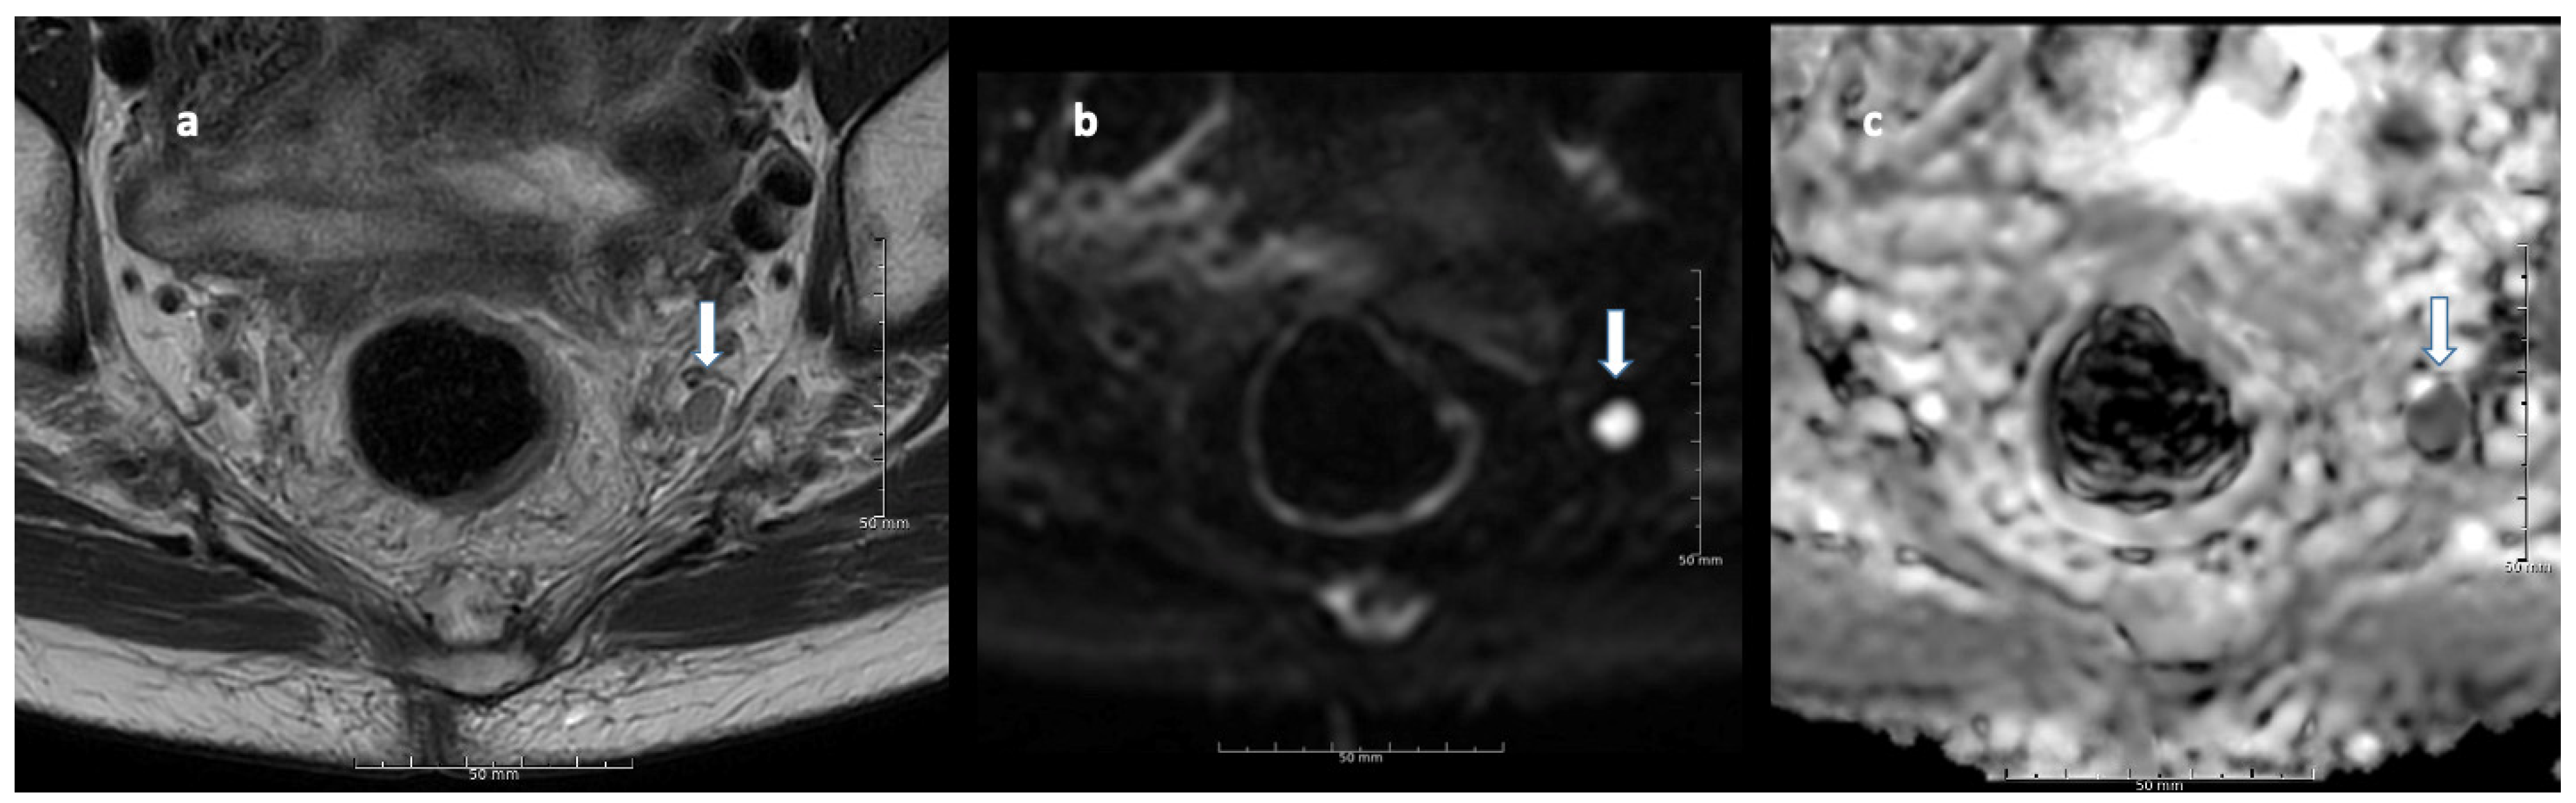

2.3. Lymph Node Assessment